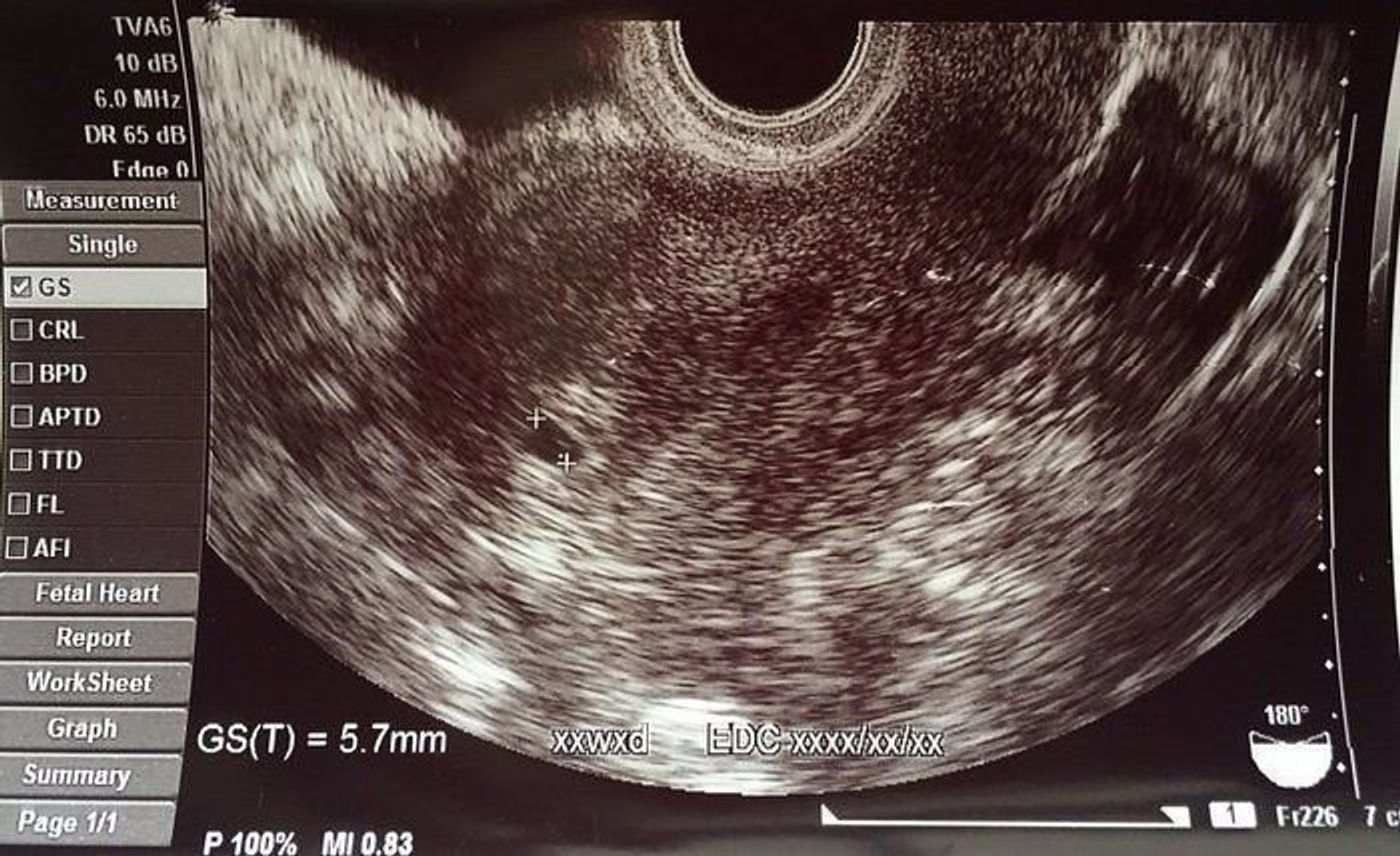

4週 エコー 胎嚢-胎嚢の大きさ(赤ちゃんが入っている袋の大きさ) 上記エコー写真ですと4週1日目ということになります。 妊娠4週目 受精卵が無事に着床して胎嚢が成長を始めています。胎嚢は赤ちゃんが入る袋のことで、早ければ妊娠4週のはじめに確認でき、一般的には 妊娠4週末から妊娠5週頃 までに見えます。 胎芽は妊娠6週頃に確認できたというケースが多く、心拍は早ければ妊娠5週のはじめ・妊娠8週までには全ての妊婦さんに見られ

これがこの時もらったエコー写真です。子宮だけ写ってる。。 一般的には、4週後半から5週前半に胎嚢が確認でき、5週後半から6週前半で胎芽や心拍の確認ができる そうです。 となると、5週2日の私は胎嚢が確認できるはずだったのですが。 エコー写真では、GS (gestational sacの略)と表記されます。 一般的に、胎嚢は妊娠4週後半~5週頃にかけて確認することができるとされています。 通常は、胎嚢・胎芽・心拍の三つを確認できた時点で、正常妊娠であると診断されます。 ただし、胎嚢が確認8週4日のエコー写真で胎嚢の隅っこに赤ちゃんがいましたが同じような方いらっしゃいますか😢? 胎嚢も少し長く何が正常なのかわからないので不安です(;_;) 1月16日 お気に入り 妊娠8週目 赤ちゃん 胎嚢 エコー写真 みいぽん 酢 (3

知っておくと楽しみ倍増 エコー写真 の見方と用語 17年4月19日 ウーマンエキサイト 1 2